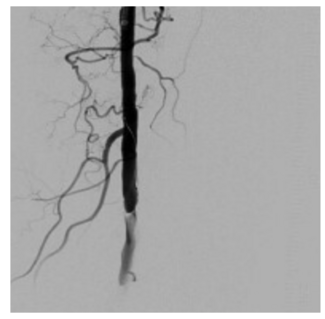

The authors report hybrid management of 2 cases of post-traumatic symptomatic pseudoaneurysms of the gluteal arteries in 2 young male patients.